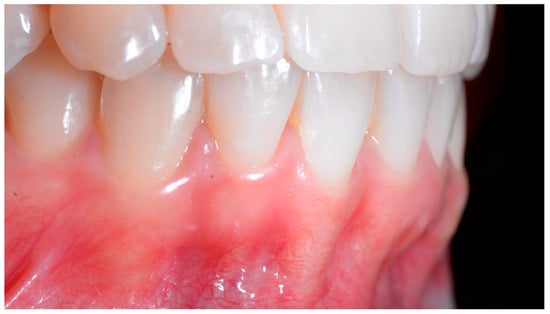

A 40-year-old patient presented with discomfort in tooth 31, citing past orthodontic treatment. As shown in Figure 11, the patient was in Class I and had poor oral hygiene associated with the presence of calculus in the incisivo-canine region. The root of 31, visible to its apex, was out of the bone and associated with severe gingival recession (Cairo RT2). Teeth 41 and 42 also showed gingival recession (Cairo RT2 and RT1).

Figure 11.

Severe wire syndrome. Frontal and lateral views.

Figure 12 and Figure 13 show a difference in the height of the free edges of the mandibular incisors and the extent of root visibility of 31.

Figure 12.

Severe wire syndrome. Frontal view.

Figure 13.

Severe wire syndrome. Lateral views.

In the present case of severe WS, generalized moderate periodontitis was diagnosed, except on the mandibular incisors, which showed a more severe attachment loss. This can be explained by the presence of the WS, which aggravates the pathological process. The presence of bacterial and calculus deposits on the incisors was certainly important, but it alone cannot explain the severity of tissue destruction, particularly on 31. This case highlights the problem of the multi-factorial etiology of WS.